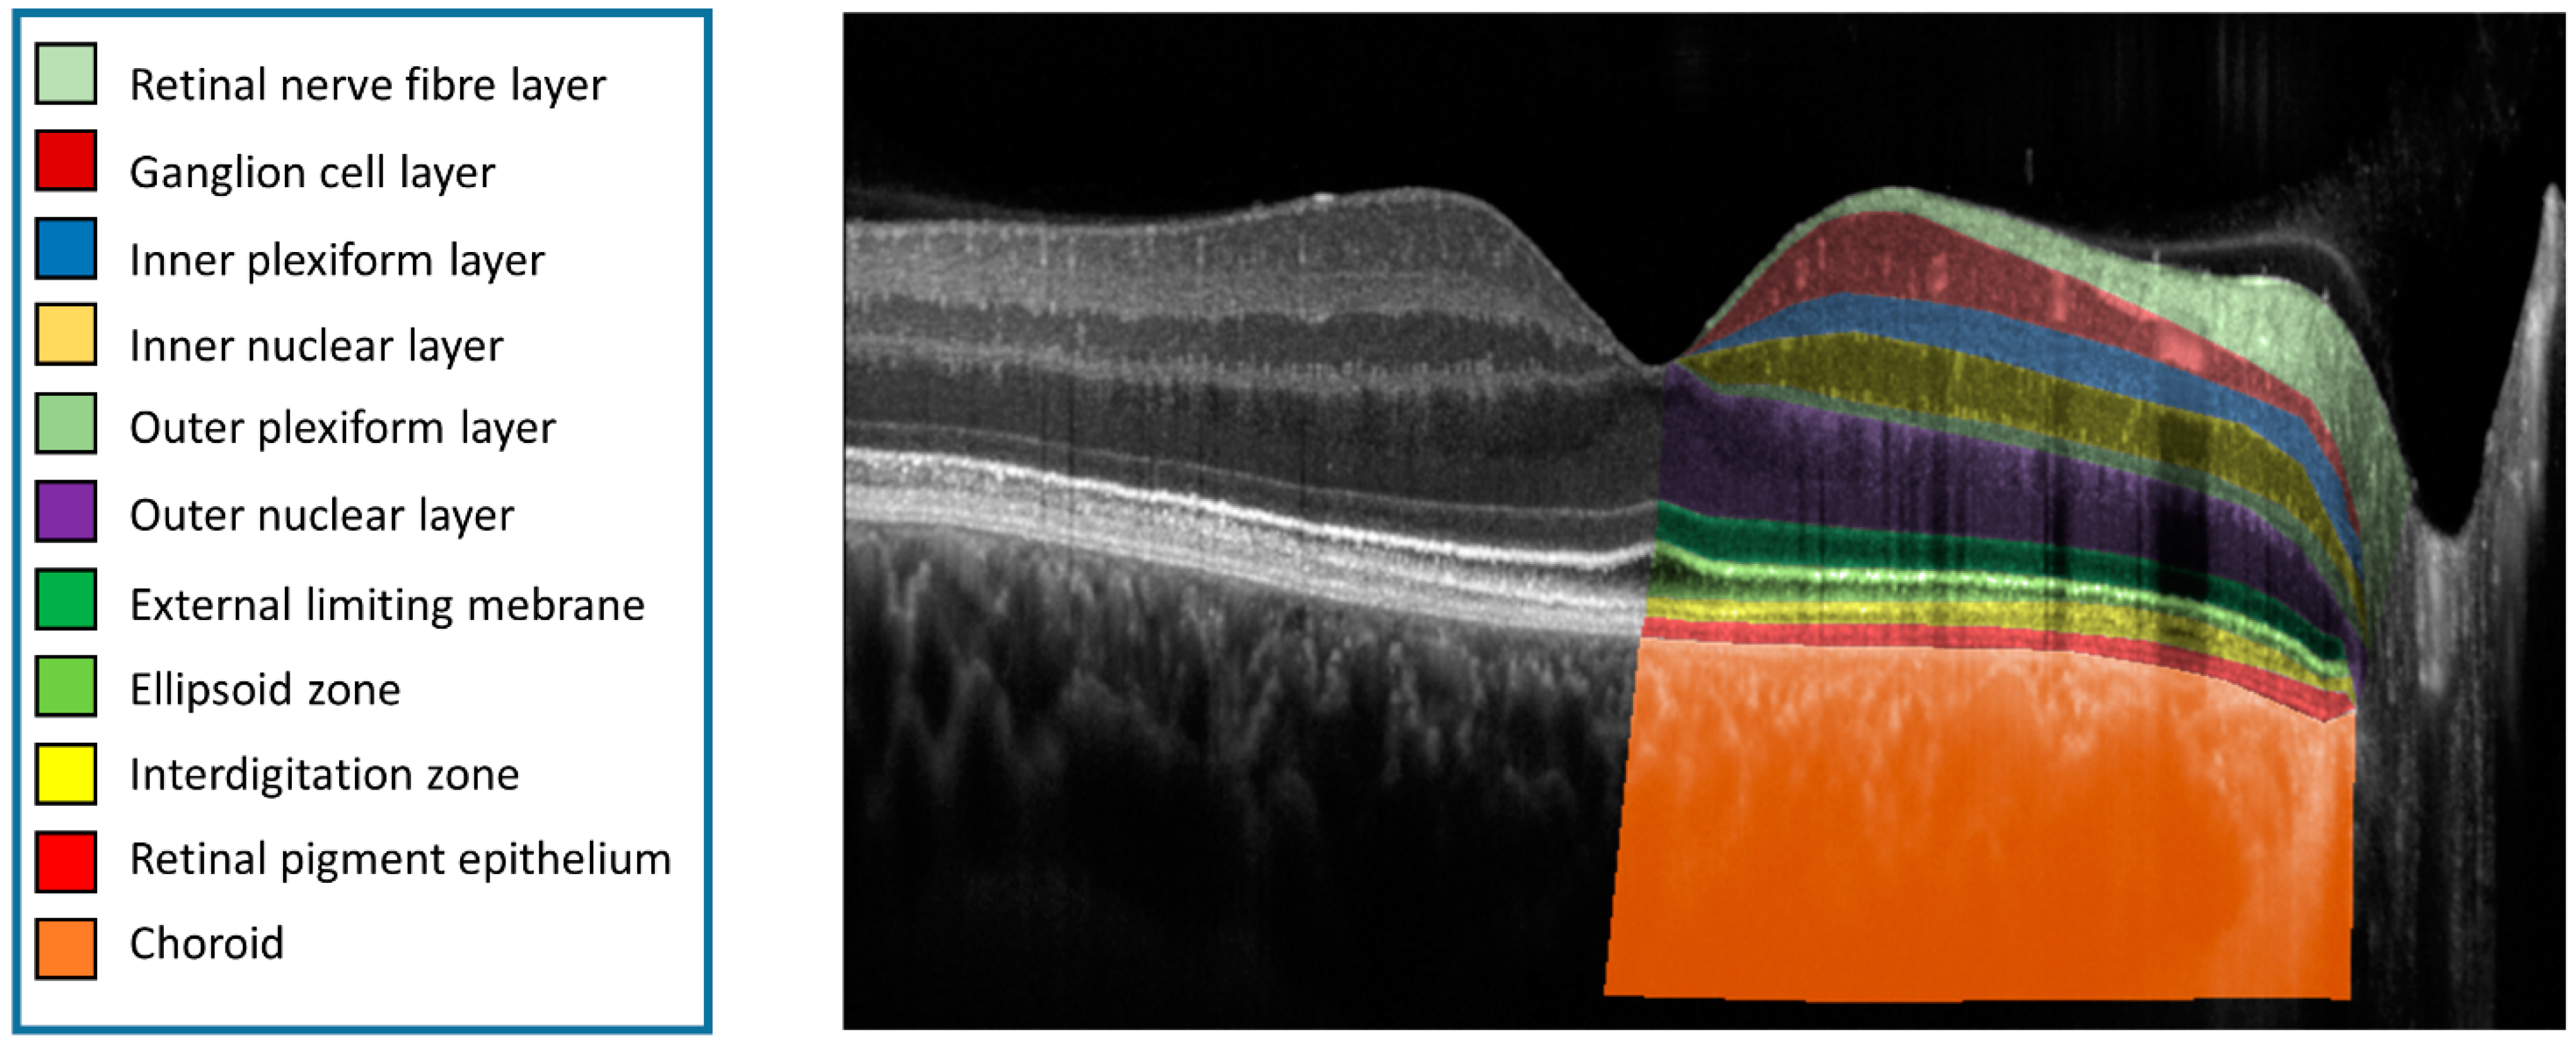

The layer definitions were slightly adapted from previous publications (Figure 1) [15,17,18,19]. We defined the retinal layers as following. Retinal nerve fiber layer (RNFL): between the internal limiting membrane (ILM) and the lower bounds of the RNFL; ganglion cell layer (GCL): between the RNFL and the lower bound of the GCL; inner plexiform layer (IPL): between the GCL and the lower bound of the IPL; inner nuclear layer (INL): between the IPL and the lower bound of the INL; outer plexiform layer (OPL): between the INL and the lower bound of the OPL; outer nuclear layer (ONL): between the OPL and the external limiting membrane (ELM, Henle fiber layer was included in the ONL in analogy to Sadigh et al. [20]); ELM: between the ELM to the ellipsoid zone (EZ,); EZ: between the EZ and the interdigitation zone (IZ); IZ: between the IZ to the retinal pigment epithelium (RPE); RPE: between the RPE and the Bruch’s membrane (BM); choroid: between the BM and the choroid/sclera interface. Finally, in AMD eyes, the RPE drusen complex (RPEDC) that conjoins the RPE/IZ and encompasses all drusen material, whether below the RPE (soft drusen and cuticular drusen) or between RPE and photoreceptors (subretinal drusenoid deposits (SDDs)) and vitelliform debris) was determined [18,21].

Figure 1.

OCT Layer Annotation. Eleven different layers (from retina and choroid), annotated and color-coded on a central B-scan from a High-Res OCT image. The right eye of a 28-year-old male control participant (best corrected visual acuity of 1.0).